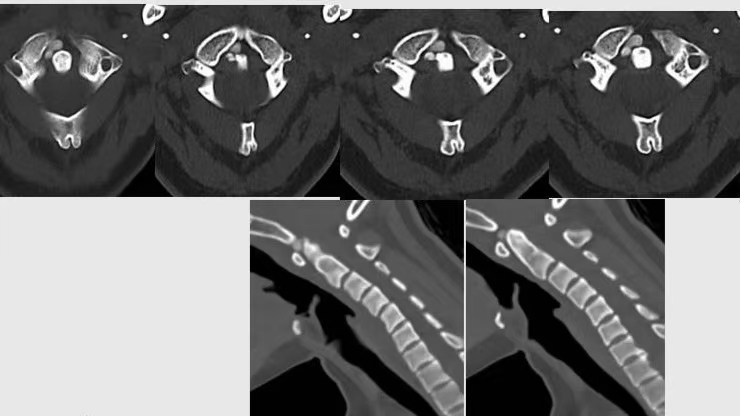

齿状突周围出现大小不一、高密度、不规则的钙沉积影,但主要发生在齿状突后侧。在影像学上,沉积的结晶在齿状突周围产生齿冠或晕圈样的特征表现。

CT所见:齿状突右前方有结节状高密度影,边界光滑。 CPPD的危险因素包括年龄、严重疾病、内分泌紊乱、代谢性疾病、电解质异常、血色素沉着症、骨关节炎、既往关节创伤/损伤等。CDS患者多见于老年女性,男女比是0.6,且2/3的患者>70岁,患者常伴有严重的颈痛。 01 诊断与鉴别诊断 目前,颈椎CT平扫出现齿状突周围的横韧带、尖韧带或翼状韧带周围钙化,且存在急性颈痛、升高的炎性指标被认为是CDS诊断金标准。 CDS并不罕见,其发病率常被低估。在急性颈痛患者中,CDS的发生率为2%。骨科和急诊医师一般对该病认识不够,颈椎平片常发现不了,且CDS患者常有发热和炎性指标升高,因此,临床上CDS常被误诊为感染、颈椎病、强直性脊柱炎、类风湿关节炎、痛风、脑膜炎、转移性脊柱肿瘤等,导致不必要的手术和药物治疗、频繁的就医及延长的住院时间。另外,CDS还应与儿童钙化性椎间盘炎相鉴别,后者为自限性疾病,多发于6-10岁,多以颈痛为主诉,实验室检查少数会出现白细胞增高,血沉加快,影像学多表现为单间隙椎间盘钙化。 02 治疗与预后 CDS通常预后良好,症状一般在几周内消退。非甾体抗炎药或短程中等剂量的皮质类固醇可快速、完全缓解症状。目前认为,两者合用是最佳方案,但常不需要长期使用。因此,在急诊或骨科门诊中,对于患者出现急性颈痛伴发热时,尤其是老年女性患者,应考虑CDS的存在。行颈椎CT平扫可早期诊断,避免误诊误治。岁月本长,而忙者自促,希望以后的日子大家能够关爱颈椎,关爱健康。 |